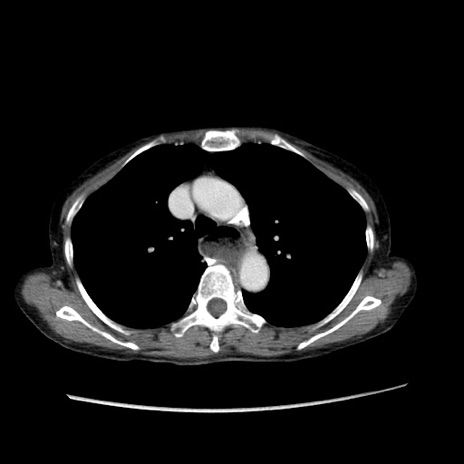

症例25(横断像)

【症例】80歳代女性

【主訴】胸のつかえ感

【現病歴】約9時間前に食後から胸のつかえた感じあり、嘔吐あり、来院。

【既往歴】胃癌(全摘)、胆摘、虫垂炎

【身体所見】心窩部に圧痛あり、反跳痛なし。

【データ】WBC 5700、CRP 0.05